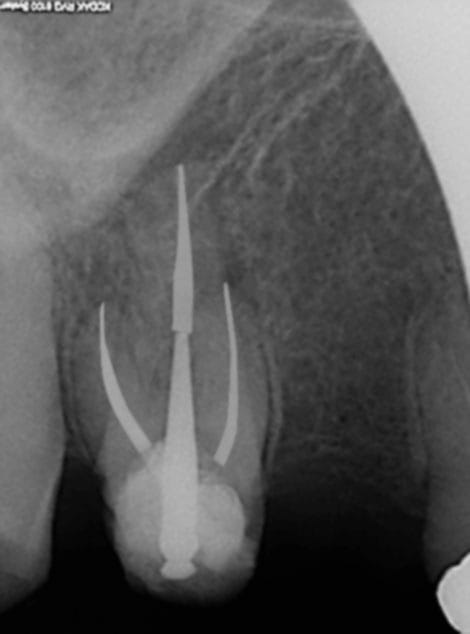

Tu t'es fait chier là. Ca vaut plus que sc 34. Toujours pas rentable l'endo !)))))

Tiens en voila une autre; Tu vas trouver le moyen de faire économiser un spr 57 et spr 50 en plus à la sécu !)))))))

R1 poel1z - Eugenol

Nouvelle discipline de l'art dentaire.

L'EAO , Endodontie Assistée par Ordinateur

Eao es1wwo - Eugenol